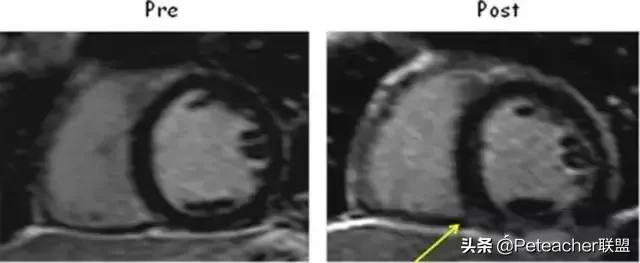

在运动期间,右室对过度的应力反应更敏感。在特殊超耐力运动员中,有一小部分会存在右室与左室交界处晚期钆增强(LGE)。但是,这种LGE并不一定代表着纤维化。例如,有一例世界最伟大超耐力运动员尽管发生了很多极端事件,但却并不存在LGE。但是,在一项全美比赛结束后,很多人的右室插入点即刻出现了LGE(图2)。因此,这种类型的LGE已被证实在ASD修复等很多情况下是可以逆转的,故其可能提示存在急性且持续时间较长的应力而非实际瘢痕。但是,携带右室心肌病桥粒突变的个体进行运动时则需谨慎,因为在这些患者中训练可导致右室功能的恶化并加速右室心肌病的表型变化。

图2 运动后右室插入点即刻出现LGE